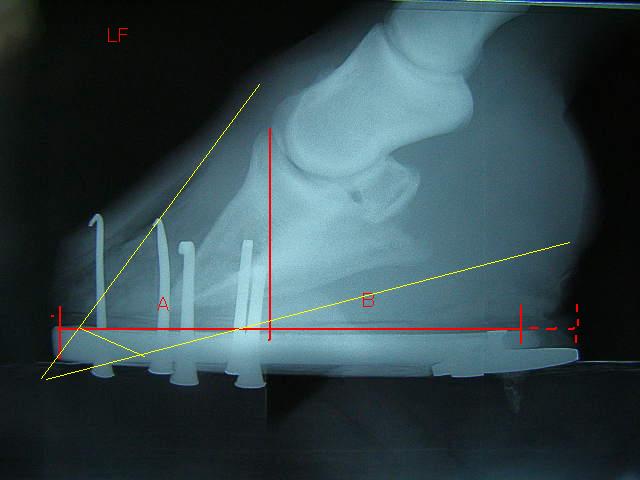

9月の左前肢

今回の左前肢

ラメラーウェッジがだいぶ取り除かれ、蹄が蹄壁にきちんとくっついて生えてきているのが確認できてホッとしました。

前回の装蹄後から左前肢の歩様がおかしかったのは、削り取った蹄の下端が先端のラメラーウェッジを押しているか、蹄尖部に重心がかかるようになっているのがちょっと痛いのではないか、とのこと。